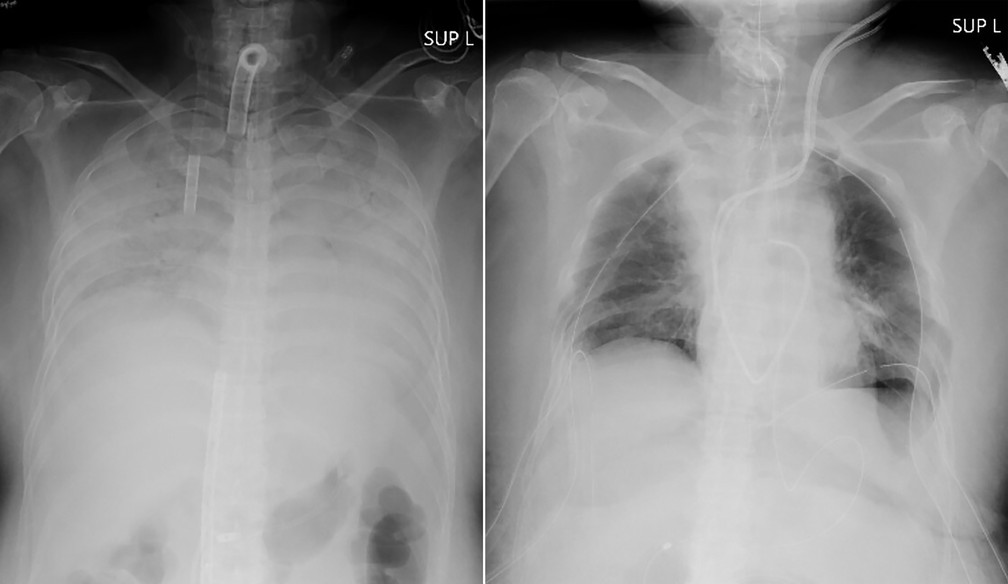

Radiografias fornecidas em 9 de abril de 2021 pelo Hospital mostram o tórax de um paciente antes da cirurgia e depois (Hospital Universitário de Quioto via AP)